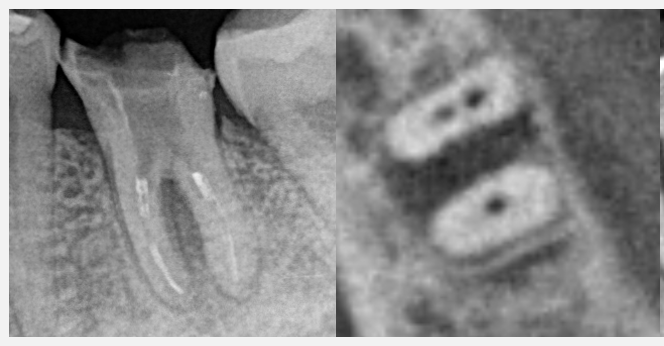

今根の中を見させていただきましたが、おそらくこの黄色い点線の部分が、本来の根の方向とは異なる部位に穴があいている状態です。レントゲン、CTでもこの部分に相当する部位の骨が大きく吸収している(溶けている)状態です。